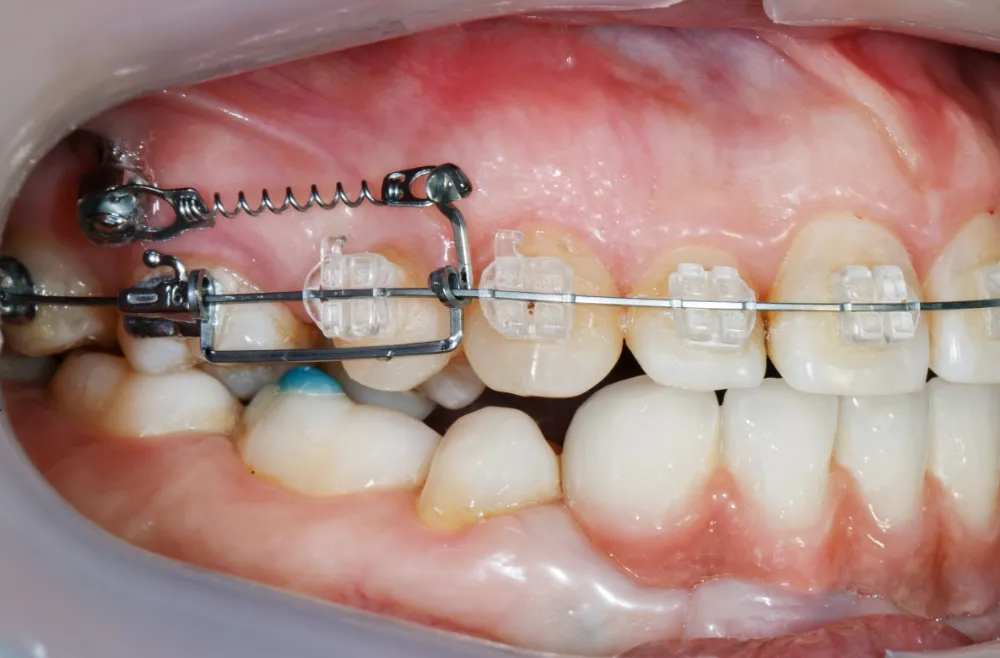

インプラント矯正は、顎骨に小さな矯正用アンカースクリュー(インプラント)を埋め込み、それを歯の移動の固定源として利用する治療法です。この方法により、歯を効率的に移動させることができ、治療期間の短縮が図れます。一般的な矯正方法では動かしづらい奥歯の後方移動に効果的なほか、抜歯が必要な症例を非抜歯で治療できる可能性も高まります。また、3Dメタルプリントで一人ひとりに合わせて作製した矯正補助装置と連結することで、治療の幅がさらに広がります。

アンカースクリューとブラケットなどの矯正装置にゴムやスプリングを取り付け、アンカースクリューを固定源として利用して歯を移動させます。